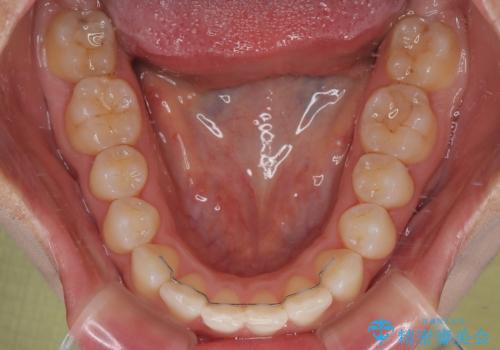

治療終了時

前歯が自然なアーチにきれいに並び、正中(上下の中心線)も整い、咬み合わせも良好です。

側方拡大することで、非抜歯であるにも関わらず前歯が前方に出ることなく、バランスの良い仕上がりとなりました。